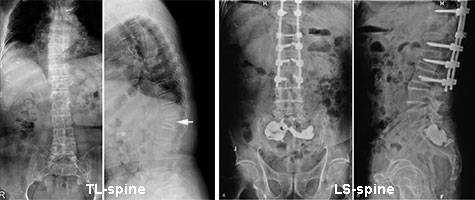

อย่างไรก็ตาม รอยโรคของคนไข้อาจอยู่ที่หลังส่วนบน บางครั้งแพทย์จะสั่งเอกซเรย์กระดูกสันหลังส่วนเอวร่วมกับกระดูกสันหลังส่วนอก (TL-spine) เพื่อจะดูแนวของกระดูกสันหลังทั้งหมด แล้วถ่ายโฟกัสตรงข้อที่มีปัญหาทีหลัง หรือบางครั้งผู้ป่วยปวดหลังส่วนล่าง เดินลำบาก แพทย์อาจสั่งเอกซเรย์กระดูกสันหลังส่วนเอวร่วมกับกระดูกกระเบนเหน็บ (LS-spine) ซึ่งจะเห็นไปถึงก้นกบ กระดูกเชิงกราน (Pelvis) และบางส่วนข้อสะโพกทั้งสองข้าง ดังรูปข้างล่าง